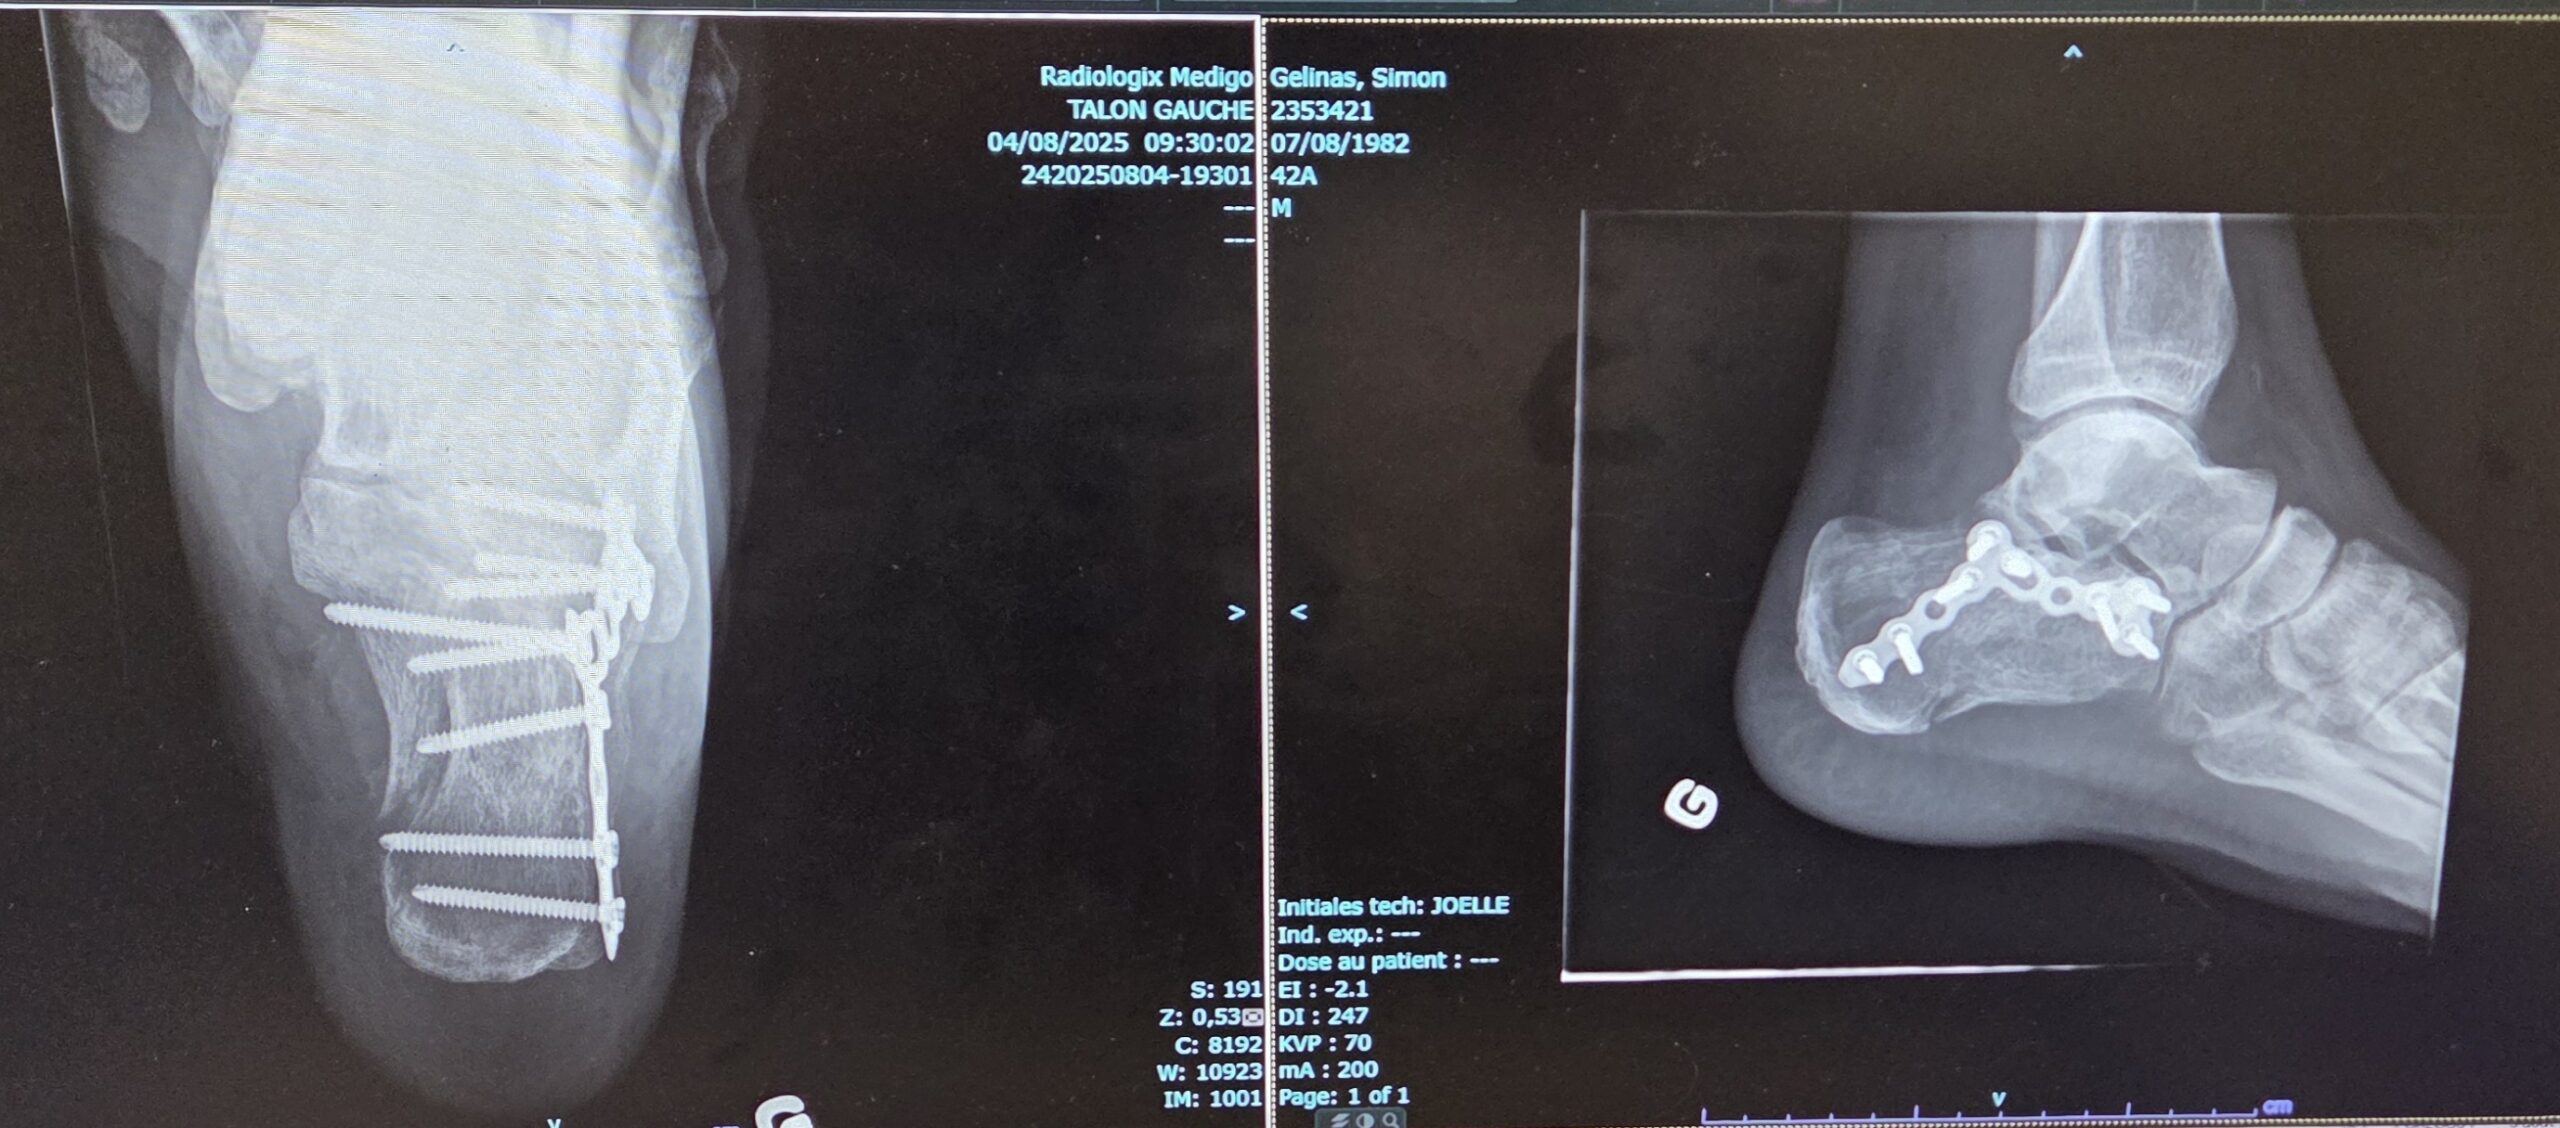

This is for the skydiving community, please share the knowledge, look out for each other and learn. I had a skydiving accident that resulted in a shattered left heel and a hematoma in my abdomen near my bladder. Overall, I am ok, but I needed to have surgery on my heel and ultimately take from nine to twelve weeks before I can put weight on my foot again.